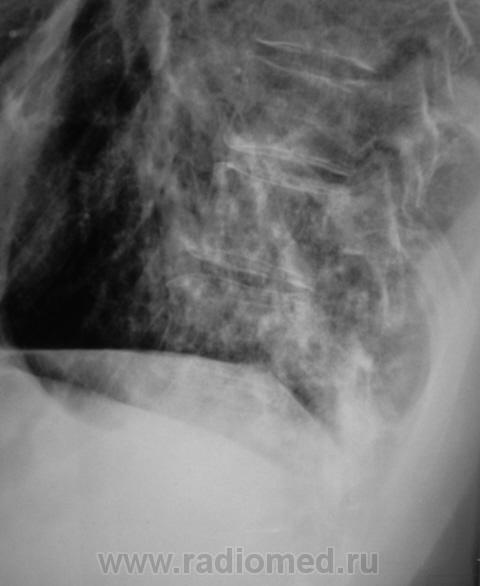

Пациент направлен на рентгенографию ОГК с диагнозом - "Левостороняя пневмония".

Анамнез стандартный. Ранее неоднократно страдал обострениями хронического бронхита. Сейчас вот не нашутку занемог - температура до 38, откашливает мокроту, кашель продуктивный.

Диагноз левосторонней нижнедолевой С10, С9 сементарной пневмонии наверное будет верным, а с учётом фона- с наличием бронхоэктазов.